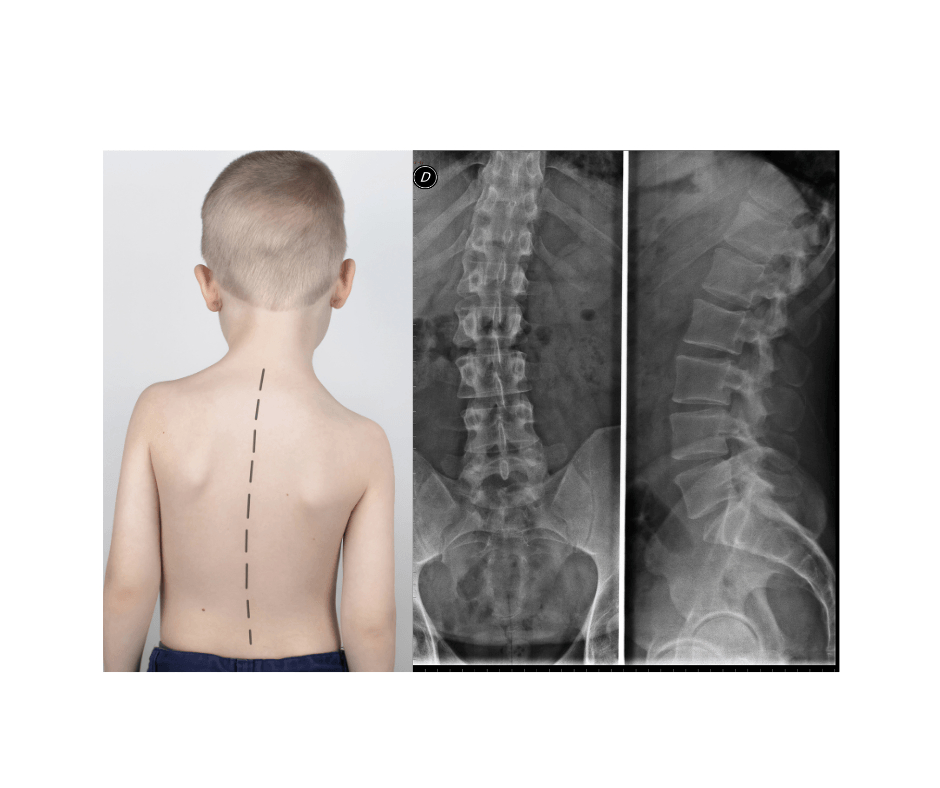

Scoliosis is an abnormal curvature of the spine. In other words; the spine naturally has a slight forward and backward curve. With scoliosis, your spine curves to the left and right into a C or S shape.

Scoliosis is a three-dimensional deformity of the spine that, based on the age of the first detection, is defined as infantile(up to three years), juvenile (from three years to puberty), or adolescent (from puberty to complete bone maturity).

A kid with scoliosis

Source: Canva Pro, Design: Susanne vd Munt